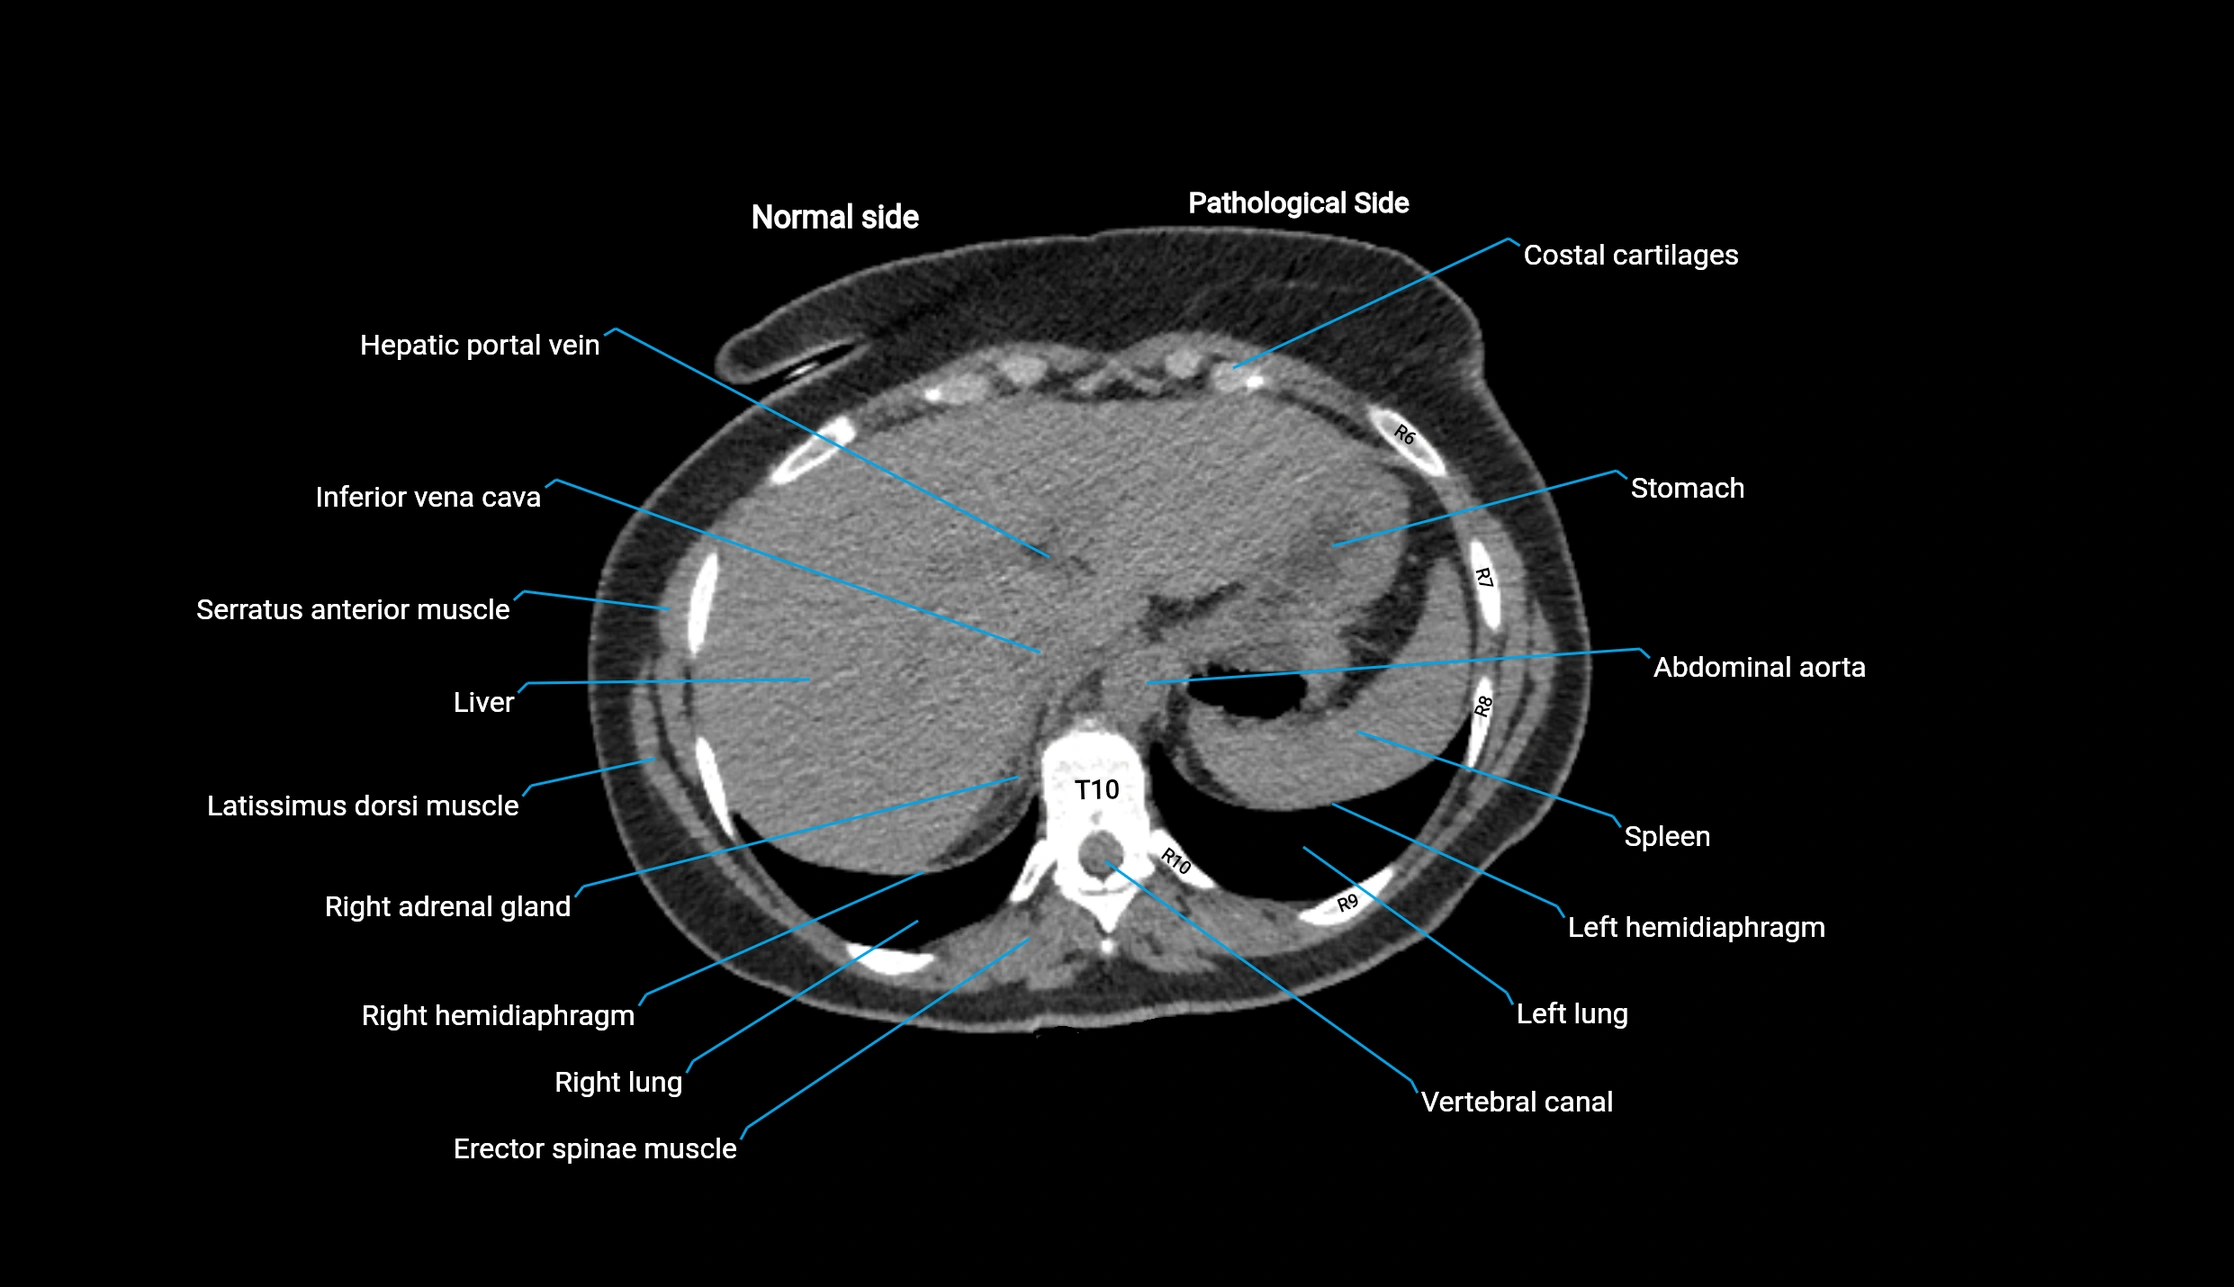

Post-Contrast CT (Contrast-Enhanced CT):

• Portal venous phase:

• Anterior right portal branch enhances intensely and homogeneously

• Clearly separates from posterior branch

• Branching pattern to segments V and VIII sharply defined

• Arterial phase:

• Slight enhancement but less conspicuous than in portal phase

• Coronal and sagittal reconstructions:

• Optimal visualization of segmental bifurcation

• Used for preoperative liver mapping

• CT liver segmentation:

• RAPV acts as the principal boundary landmark for dividing anterior vs. posterior right hepatic segments